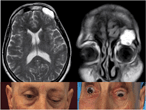

Fronto-orbital mucocele with intracranial extension: a case report

Rocco Severino and Paolo Severino

Journal of Surgical Case Reports, Volume 2017, Issue 6, June 2017, rjx107, https://doi.org/10.1093/jscr/rjx107